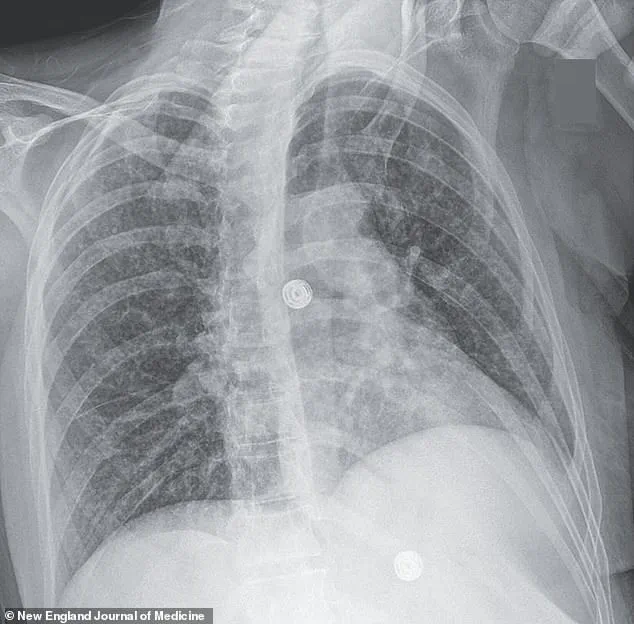

X-rays revealed small nodules in her lungs, a telltale sign of bacterial infection.

Further imaging uncovered lesions in her liver, lymph nodes, pancreas, and brain—indications that the infection had spread far beyond her respiratory system.

Consider the case of a woman whose medical scans revealed nodules in multiple organs, including her lungs, liver, pancreas, and brain.

These images, captured through advanced imaging techniques, illustrated the insidious nature of the disease.